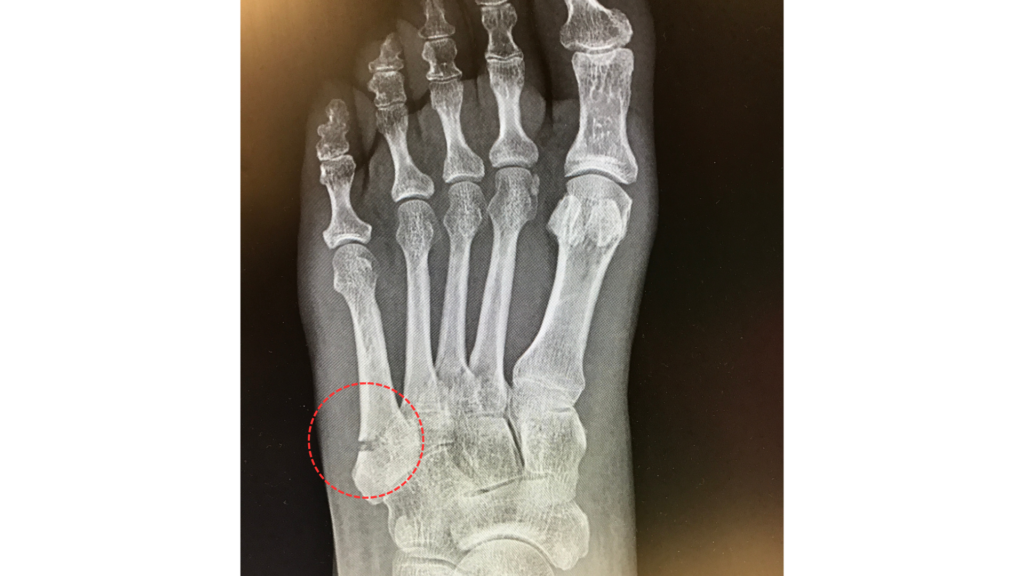

捻挫と自己判断した中学生サッカー選手の早期復帰

自分で「捻挫」と判断した足首の痛みでしたが、骨折の可能性を疑い、すぐにギプス固定と医師への紹介を実施。

骨折と診断された後、月額制アキュスコープを併用することで、患部の治癒を加速。通常よりも1週間早く競技に復帰することができました。

正確な検査と、アキュスコープによる早期回復プログラムが、大切な成長期の復帰をサポートしました。